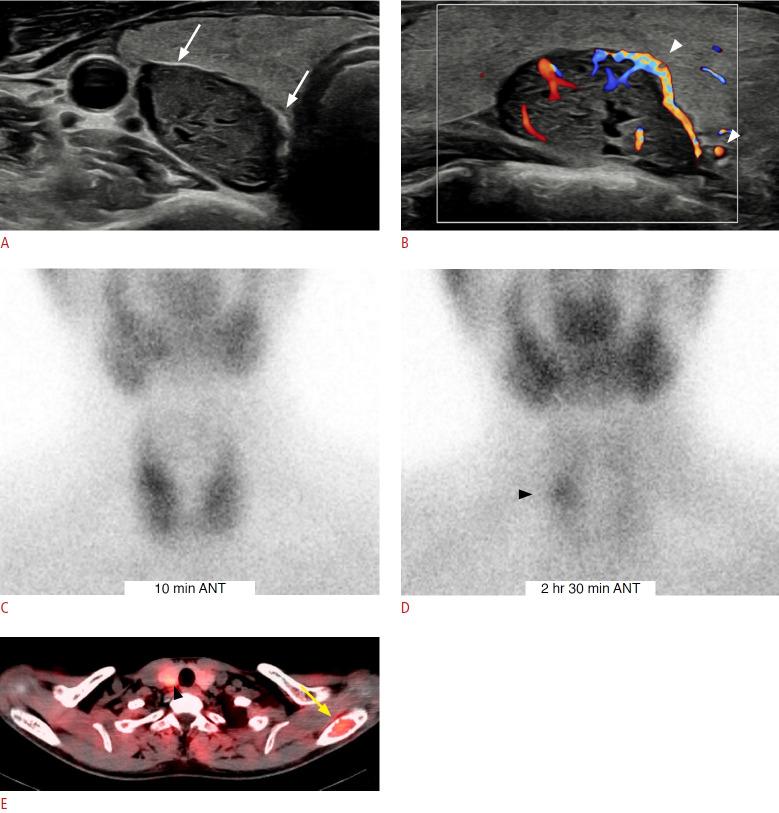

The parathyroid glands play a key role in maintaining calcium-phosphate homeostasis by secreting parathyroid hormone (PTH). Hyperparathyroidism, characterized by the inappropriate overproduction of PTH, is classified as primary, secondary, or tertiary according to its pathophysiology. Although diagnosis is principally biochemical, imaging is essential for accurately localizing hyperfunctioning glands. Precise localization allows for focused minimally invasive surgery, reduces the risk of persistent or recurrent disease, and avoids unnecessary bilateral neck exploration. Current techniques include high-resolution ultrasonography, 99mTc-sestamibi scintigraphy with single-photon emission computed tomography/computed tomography (CT), four-dimensional CT, magnetic resonance imaging, and positron emission tomography/CT with tracers such as 18F-fluorocholine. Parathyroidectomy remains the mainstay of treatment; however, recent advances in thermal ablation have expanded treatment options for patients unsuitable for surgery.

甲状旁腺通过分泌甲状旁腺激素(PTH)在维持钙磷稳态中起关键作用。甲状旁腺功能亢进症的特征是PTH分泌过多,根据其病理生理学可分为原发性、继发性或三发性。虽然诊断主要依靠生化检查,但影像学检查对于准确定位功能亢进的腺体至关重要。精确的定位有助于进行有针对性的微创手术,降低持续性或复发性疾病的风险,并避免不必要的双侧颈部探查。目前的技术包括高分辨率超声检查、99mTc-甲氧基异丁基异腈闪烁显像联合单光子发射计算机断层扫描/计算机断层扫描(CT)、四维CT、磁共振成像以及使用18F-氟胆碱等示踪剂的正电子发射断层扫描/CT。甲状旁腺切除术仍然是主要的治疗方法;然而,热消融技术的最新进展为不适合手术的患者扩展了治疗选择。